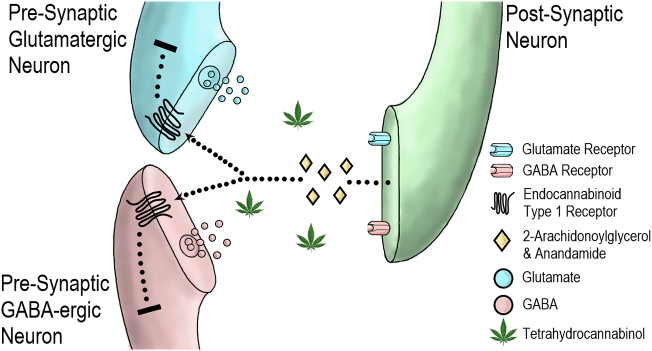

The main psychoactive substance in cannabis is Δ9-tetrahydrocannabinol (THC) (ref. Wachtel et al., 2002) which was first isolated from hashish in 1964 by Gaoni and Mechloulam. THC is gaining interest for its broad therapeutic potential. This includes putative anti-epileptic properties (ref. Friedman & Devinsky, 2015), analgesic properties in neuropathic and chronic pain (ref. Abrams et al., 2007; ref. Mucke et al., 2018; ref. Narang et al., 2008; ref. Svendsen et al., 2004; ref. Wilsey et al., 2008), anti-emetic properties in cancer (ref. Davis, 2016; ref. Smith, Azariah, et al., 2015), and anti-spastic properties in stroke and multiple sclerosis (ref. Collin et al., 2007; ref. Marinelli et al., 2017). THC was originally described as an agonist of endocannabinoid CB1 receptors (CB1R) (ref. Felder et al. 1992), however, there is growing evidence of partial agonist properties at this site from both in vitro (ref. Breivogel & Childers, 2000; ref. Govaerts et al., 2004; ref. Kelley & Thayer, 2004; ref. Petitet et al., 1998; ref. Shen & Thayer, 1999; ref. Sim et al., 1996) and in vivo (ref. Paronis et al., 2012) studies. The CB1R is a widespread G protein-coupled receptor (ref. Pertwee, 2008) found at high concentrations in key brain regions associated with reward, emotional and cognitive processing including the neocortex (particularly frontal and limbic areas), hippocampus, amygdala, cerebellum, thalamus and basal ganglia (see Fig. 1) (ref. Glass et al., 1997). THC alters signalling of endocannabinoid transmitters such as 2-arachidonoylglycerol and anandamide. These ligands are released endogenously by neurons and act on CB1Rs in adjacent γ-aminobutyric acid (GABA)-ergic and glutamatergic nerve terminals resulting in retrograde signalling (see Fig. 2) (ref. Bloomfield et al., 2016; ref. Castillo et al., 2012). THC also demonstrates partial agonist properties in vitro at the CB2 receptor, but with lower efficacy than at CB1R. (ref. Pertwee, 2008). As THC has a number of double bonds and stereoisomers, this review focuses on the main THC isomer found in cannabis, (−)-trans-Δ9-tetrahydrocannabinol, which is also referred to in some older studies by its alternative name Δ1-tetrahydrocannabinol and as a pharmaceutical preparation using the International Non-Proprietary Name dronabinol.